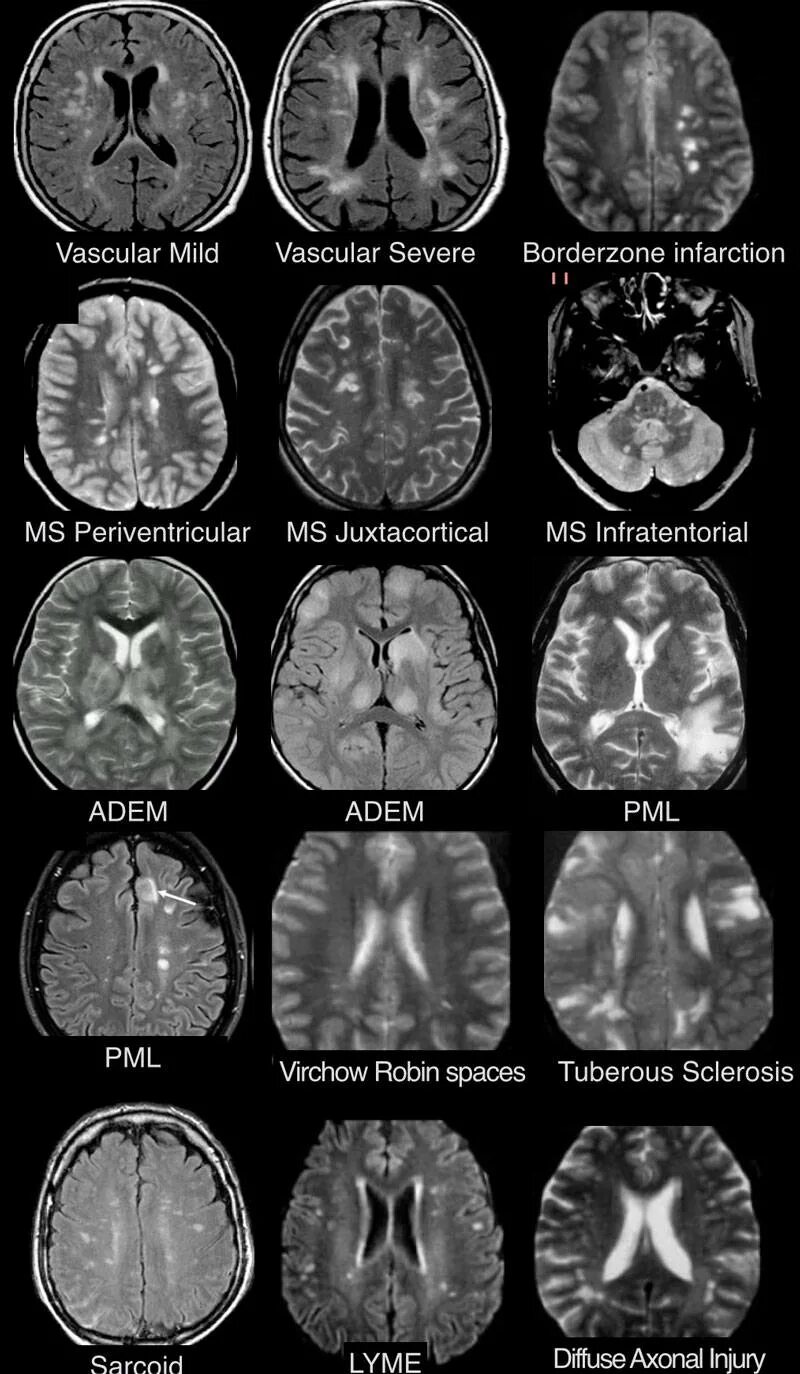

Что значит пространства вирхова робина